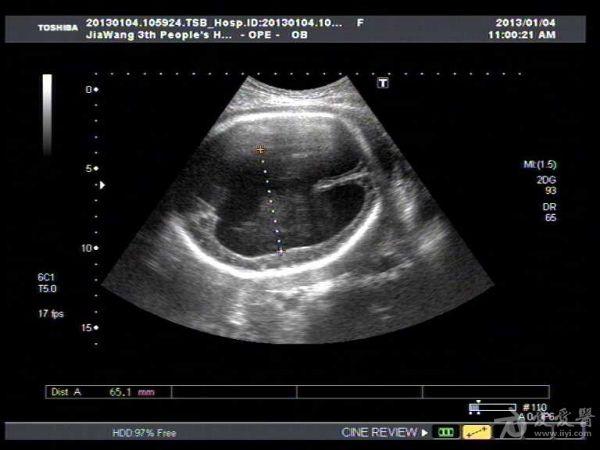

此孕妇听信家人说吃核桃能补脑,吃了两个月核桃来来复查,脑积水更明显。